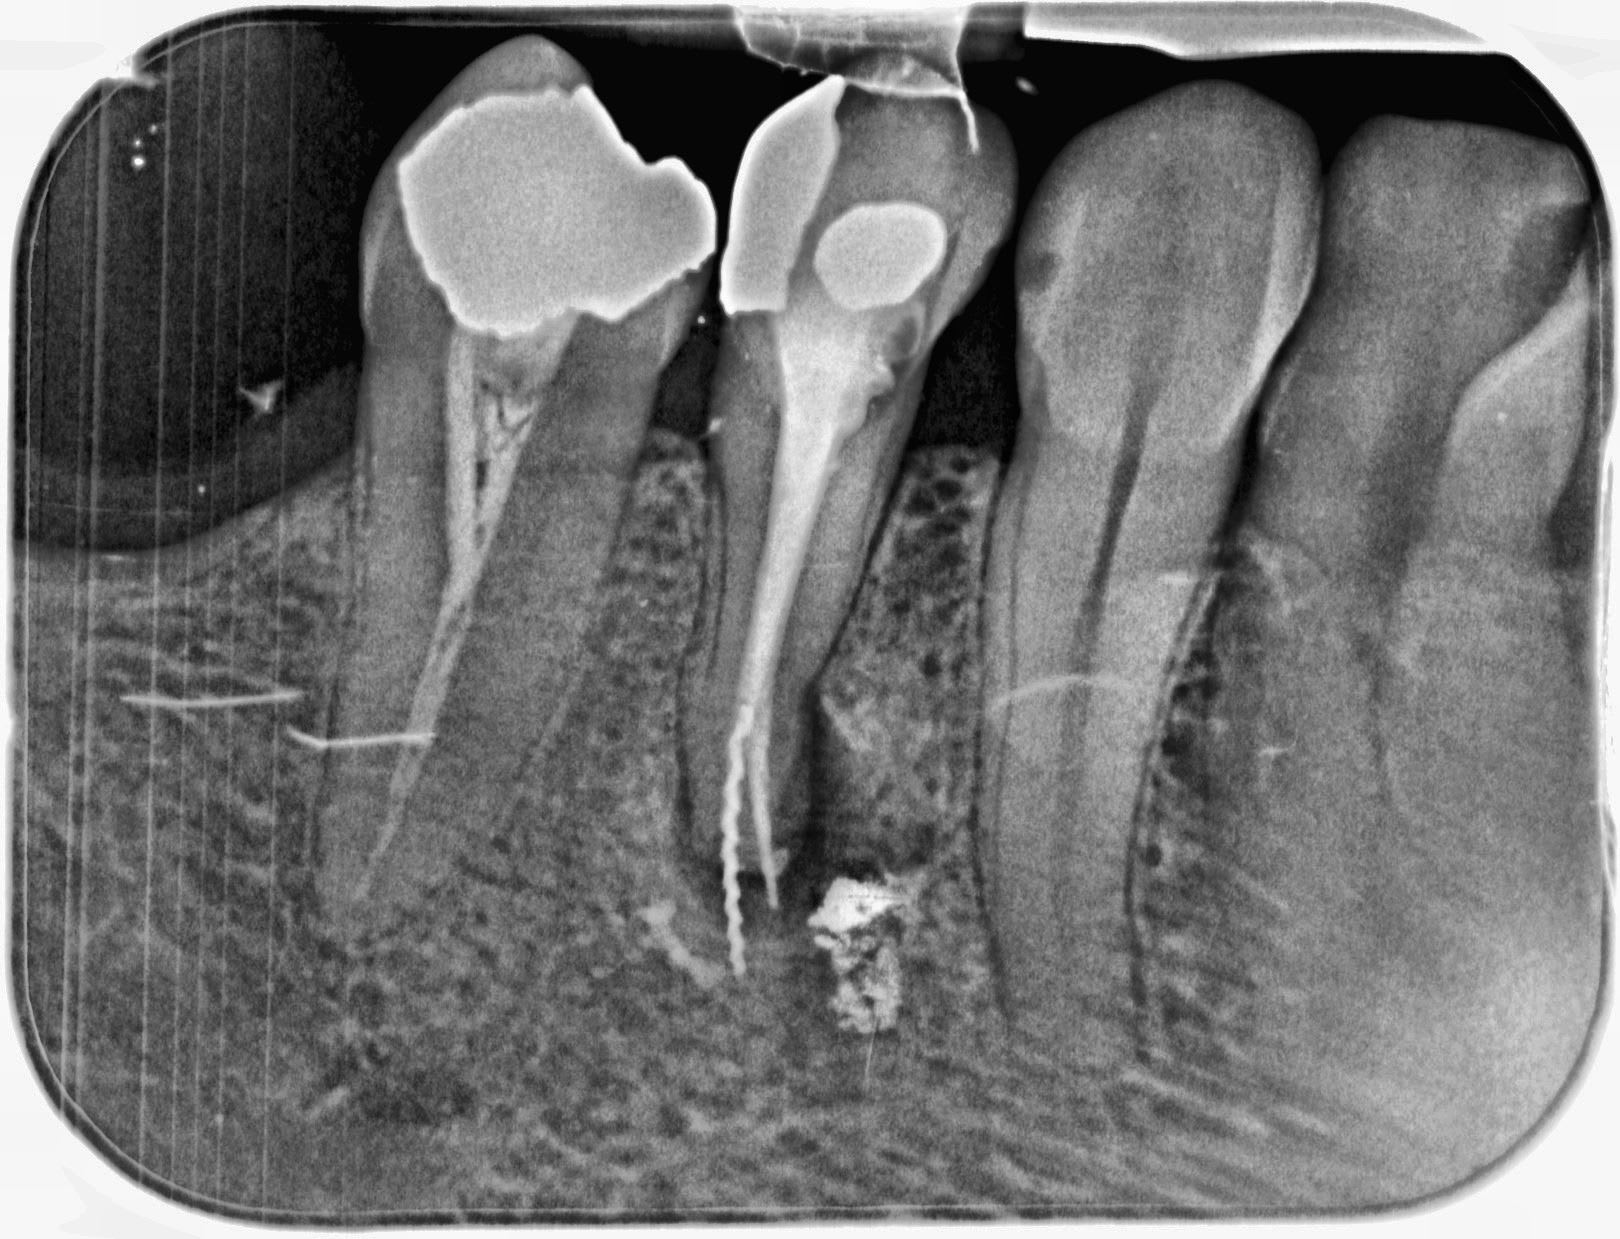

J'ai bloqué un openeur dans un canal ... du coup, j'ai inversé le sens de rotation de mon contre angle pour le débloquer. Et j'ai oublié de le mettre dans le bon sens au moment de thermo compacter.

Le cas était amusant, le confrère qui avait obturé n'avait pas trouvé le canal lingual.

Ça pue quand même un peu ton truc là… ton instrument traverse du tissus infectieux, le cône d’à côté dépasse lui aussi… et pour couronner le tout, la résection a cet endroit si ça foire c’est pas jojo. Ça sent le titane…

perso j extrais je curte et apres implant